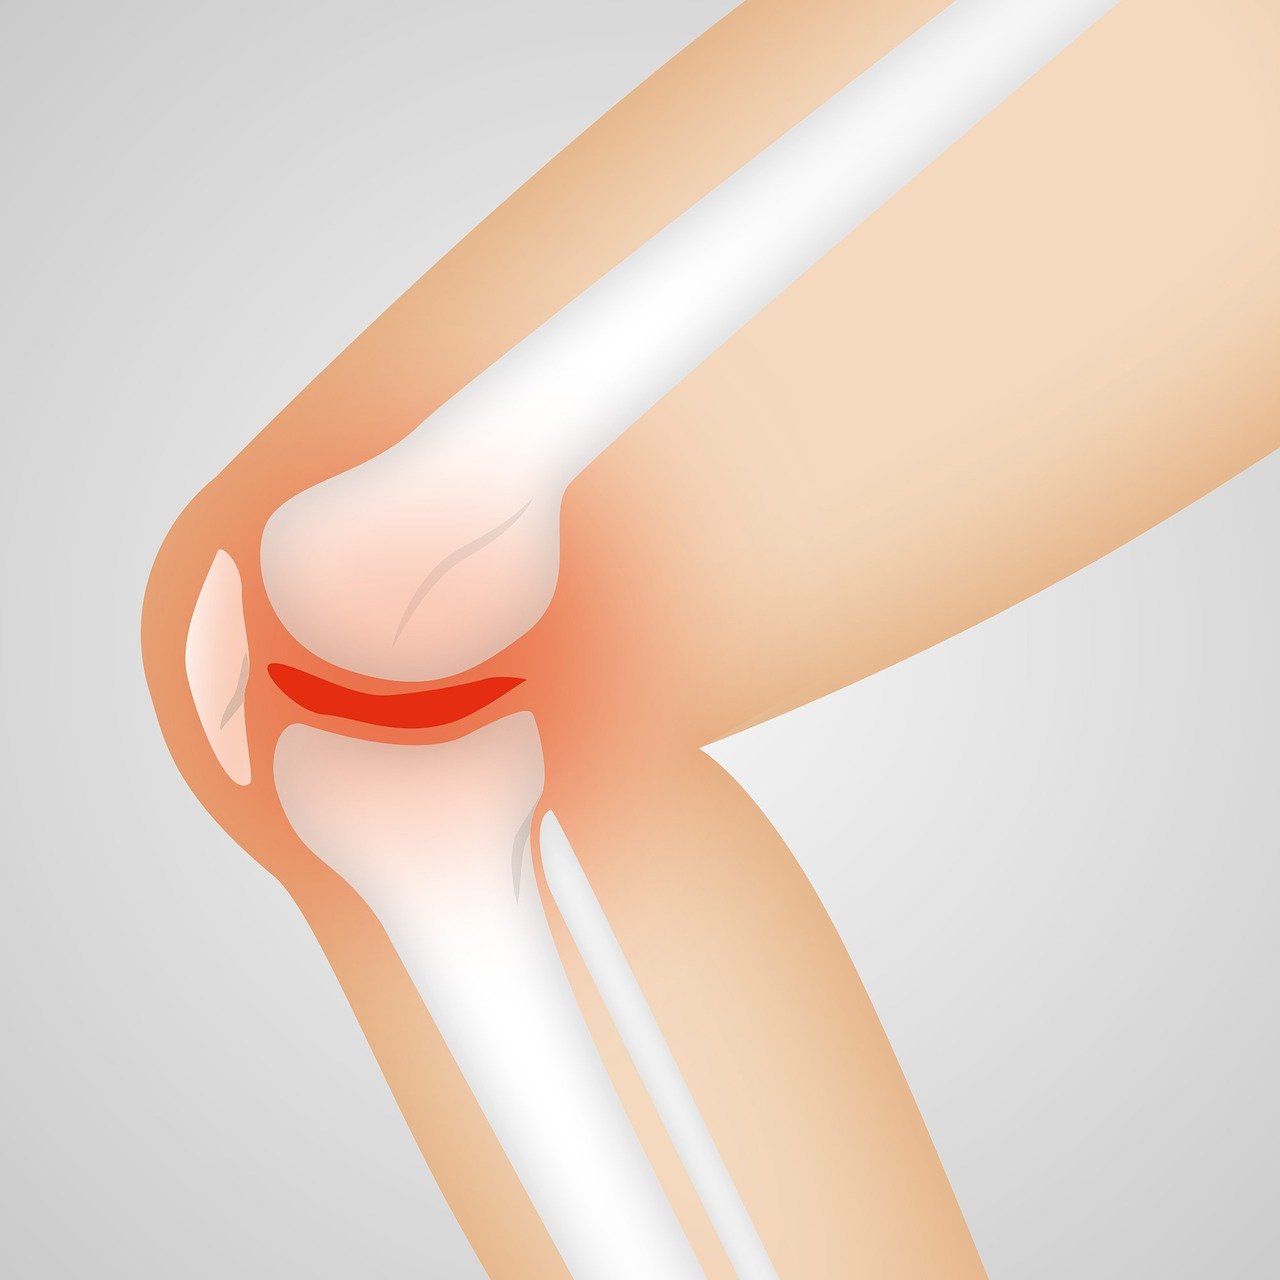

무릎통증 원인 이해하기

무릎 통증은 현대인들이 자주 경험하는 건강 문제 중 하나로,

다양한 원인에 의해 발생할 수 있습니다.

무릎은 우리 몸에서 가장 큰 관절 중 하나로,

체중을 지탱하고 움직임을 돕는 중요한 역할을 합니다.

특히 운동선수나 노년층에게 흔히 발생하며, 일상 생활에 큰 불편을 초래할 수 있습니다. 무릎 통증의 원인을 이해하는 것은 건강한 무릎을 유지하는 첫 걸음입니다. 무릎 통증의 다양한 원인에 대해 세부적으로 알아보겠습니다.